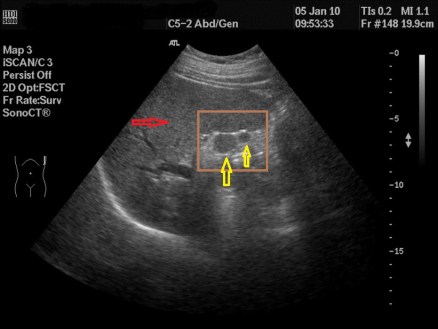

Esta es una imagen, conseguida con un corte longitudinal, en situación normal…mira la misma imagen en una situación de rotura del Tendón del Bíceps Femoral:

Patología

En la imagen patológica que ves arriba es vital la localización del Peroné. Ahora te voy a pedir que compares y que observes como en la imagen de normalidad vemos un tendón hiperecogénico, marcado por flechas amarillas, homogéneo insertando en el Peroné…en la imagen siguiente el tendón está aumentado de tamaño, heterogéneo y con componente líquido, lo marcan las líneas rojas…Es precioso, ¿verdad?…ambas imágenes son de deportistas, una corredora y amiga, la imagen de normalidad y un futbolista, la imagen patológica.